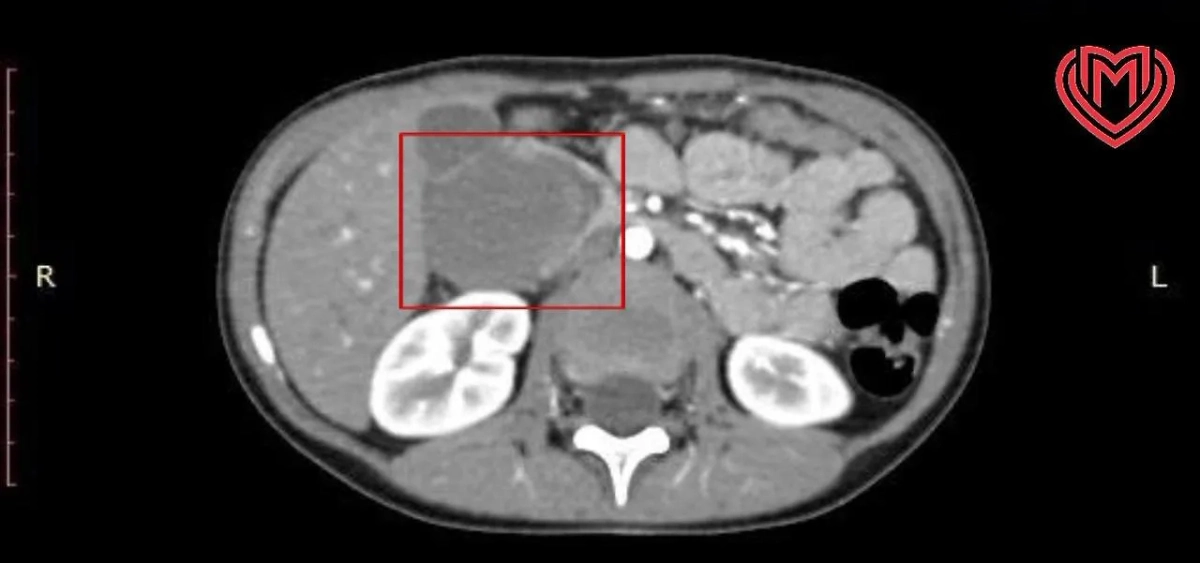

Гематома перекрыла просвет. Фото © Предоставлено Life.ru пресс-службой Депздрава Москвы

Причиной такого состояния стала обширная гематома размером 52 на 48,5 миллиметра, образовавшаяся после падения. По словам родителей, несколько дней назад ребёнок, увлёкшись активными играми, неудачно приземлился телом на жёсткий подлокотник дивана. Внешних повреждений никаких не было, да и мальчик не жаловался. Родители с облегчением выдохнули, но спустя двое суток появились тревожные признаки.

«Во время проведения гастроскопии в просвете двенадцатиперстной кишки мы обнаружили непроходимость. Гастроскоп размером всего 3,5 мм не смог «пройти» из-за наросшей гематомы, перекрывшей просвет двенадцатиперстной кишки. Дело дошло до того, что ребёнок уже не мог есть твёрдую пищу и воду пил лишь малыми порциями», — рассказал детский хирург Руслан Молотов.

Лапароскопическая операция выявила, что скопление крови развилось между слоями кишки, чудом не повредив её стенку. Хирурги аккуратно удалили гематому.